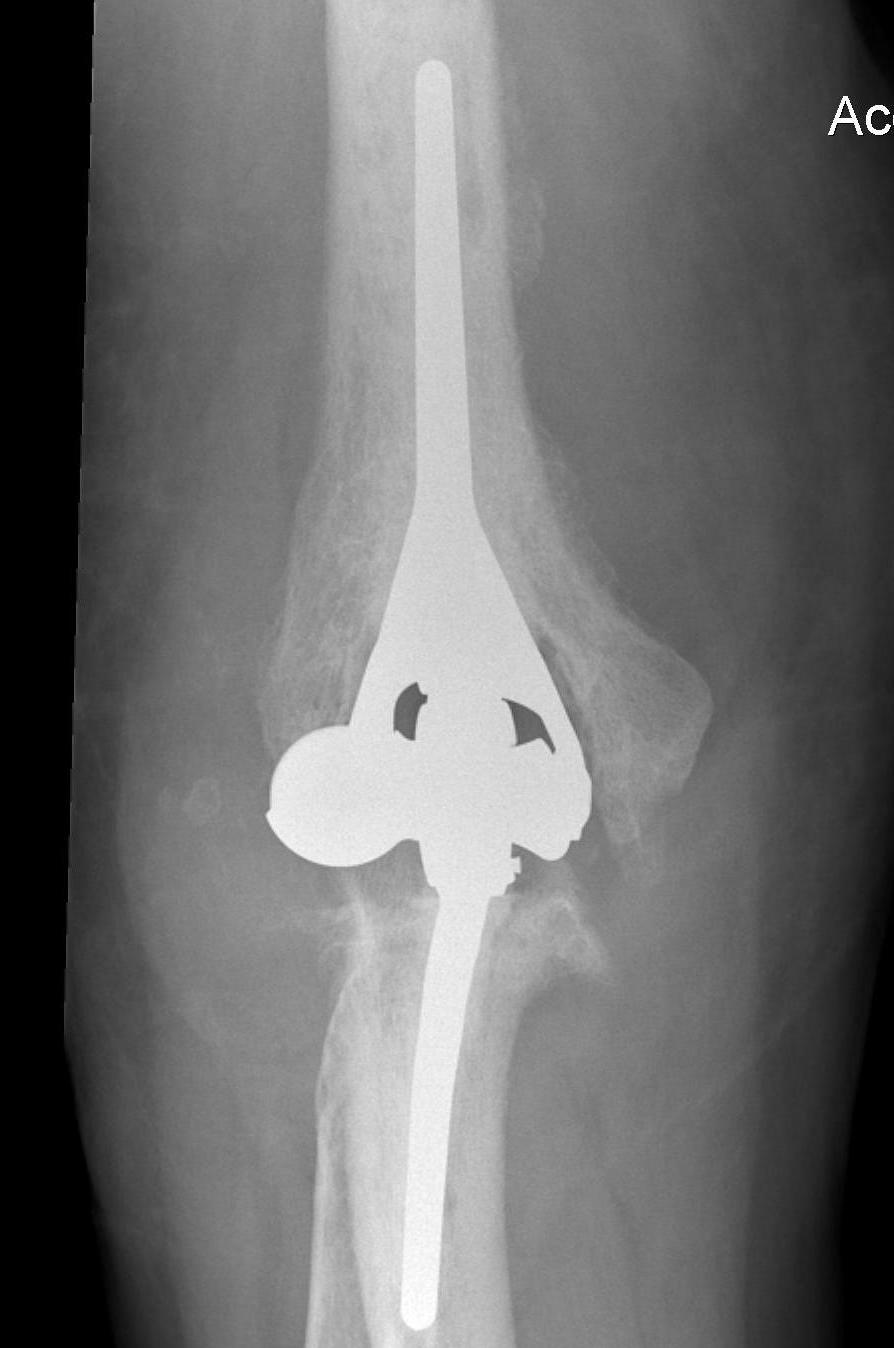

Aseptic Loosening

- systematic review of 3000 TEA

- loosening rates 10% for unlinked and 14% for linked prosthesis

Results

- revision with allograft - prosthesis composite

- 25 patients

- one nonunion / one malunion

- 84% TEA survival

Ulna allograft - prosthetic revision TEA